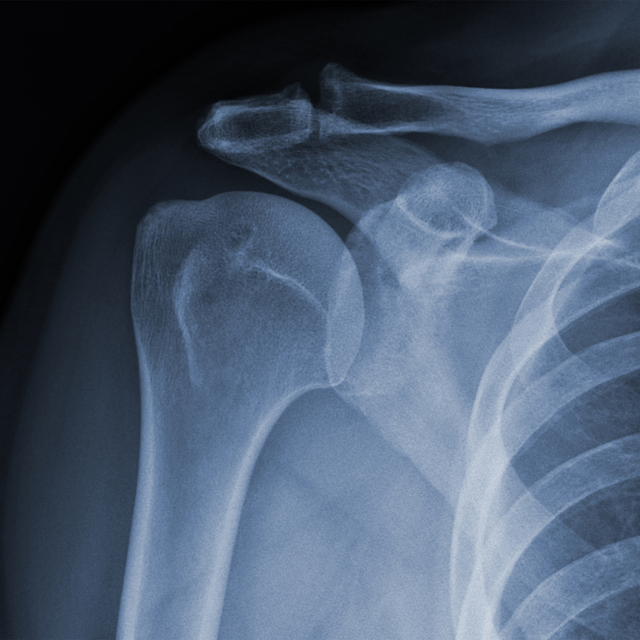

Description I broke my wrist and got ahold of the x-rays for manipulation. It only took 4 months to heal due to breaking in half one of the bones. Here I'm giving you a high five since it's finally healed. Yay!